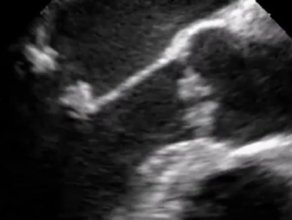

ή Μαραντική Ενδοκαρδίτιδα

Kissing sign. Oι εκβλαστήσεις είναι στα άκρα τω γλωχίνων και δίνουν εικόνα σαν αν φιλιούνται,